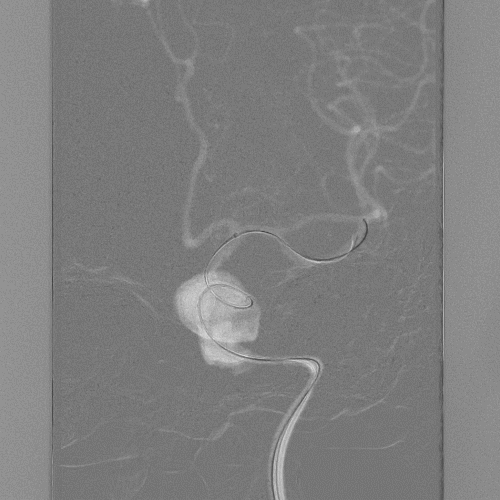

术前DSA检查:

左右滑动切换图片

术前DSA(3D):

动脉瘤长度约45mm。

术后正位造影。

术后侧位造影。